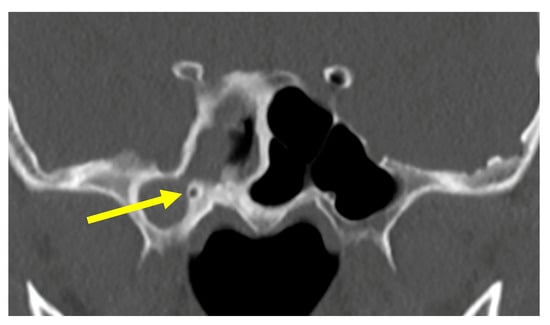

Figure 1.

The sphenoid sinuses. The arrow indicates the narrow opening into the lateral recess.